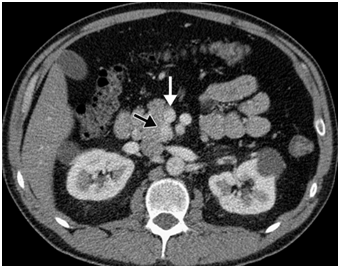

CT scan has many advantages since it can be easily performed, is non-invasive and the images are easily interpretable for the surgeon. Insulinoma typically appear as well-defined, rounded, homogeneously masses of the pancreas. Because the majority of insulinoma are usually smaller than 2cm, dynamic CT scan should be performed; the sensitivity of the dynamic CT scan in the detection of insulinoma ranges from 30% to 66%. Dual-phase contrast spiral CT scan is more sensitive than other noninvasive imaging studies. In a group of seven patients with tumors that were biochemically proven but not previously located by ultrasonography, CT scan, or magnetic resonance imaging, six of seven tumors ranging from 6 to 18 mm were detected by dual-phase spiral CT scan. Atypical CT scan imaging of insulinoma includes hypoattenuating masses on enhanced CT or intra-arterial dynamic CT, cystic masses, and calcified masses (Figure 1–3).26–30

Figure 2 Pancreatic insulinoma. Axial contrast-enhanced CT scan obtained during the arterial phase shows a homogeneous enhancing lesion (black arrow) in the uncinate process of the pancreas, just posterior to the superior mesenteric vein (white arrow). 24